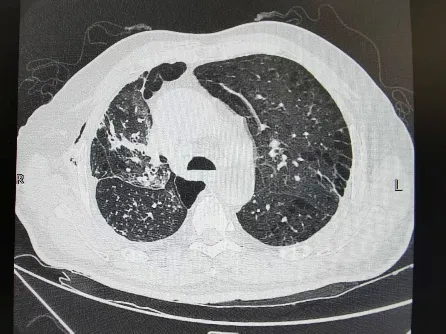

出院前肺CT